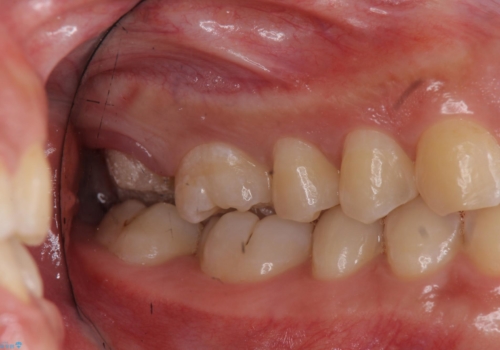

奥歯の虫歯 特殊な形をした歯の治療

- 奥歯が虫歯になり、位置的に詰め物は難しかったため、被せものにする治療を行いました。

頬側に咬頭が一つ多い歯であったのと、歯肉に近い位置が虫歯になっていたため、被せものでしっかり覆う治療を行いました。